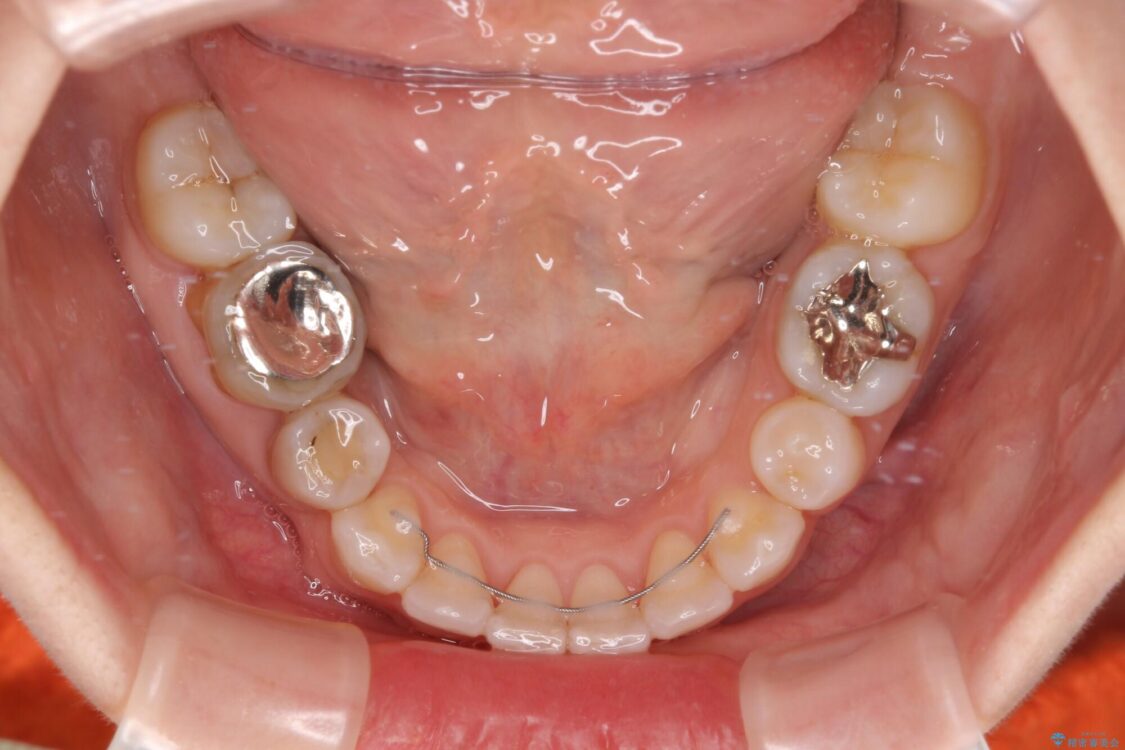

口元の閉じにくさと、奥歯の咬み合わせを気にして来院された患者様です。

左下の大臼歯2本が顕著に舌側に傾斜しているため、まずは奥歯の咬み合わせを改善をし、その後上下左右の第1小臼歯4本を抜歯することで口元を引っ込めながら整えることとしました。

治療前

治療途中

• 【モニター】出っ歯と咬み合わせを改善 ワイヤー装置の抜歯矯正 治療途中画像